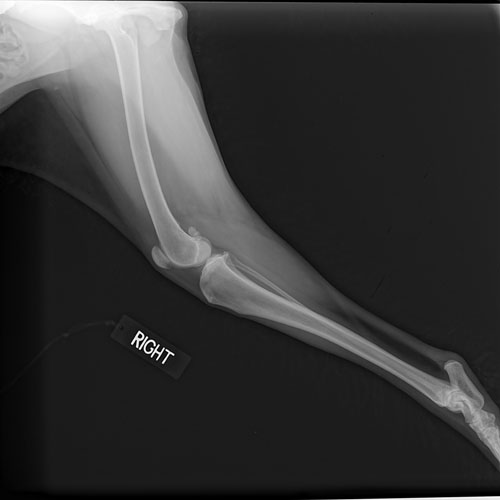

Riverside Veterinary Hospital provides the latest veterinary diagnostic technology available, including digital radiography. Digital radiography allows us to examine interior organs and assess the status of injuries or diseases that may be present. It is extremely beneficial in helping our veterinarian diagnose fractures, determine the size and location of tumors or foreign objects that your pet may have swallowed, measure organ size to detect disease, diagnose pneumonia, discover pregnancies, bladder stones, chronic arthritis, and more.

Digital radiography is painless, safe, and non-invasive. It provides clear images of the area of concern quickly and without having numerous retakes which means accurate and efficient patient assessments. It also uses very low doses of radiation making it safe enough for pregnant females and young pets.